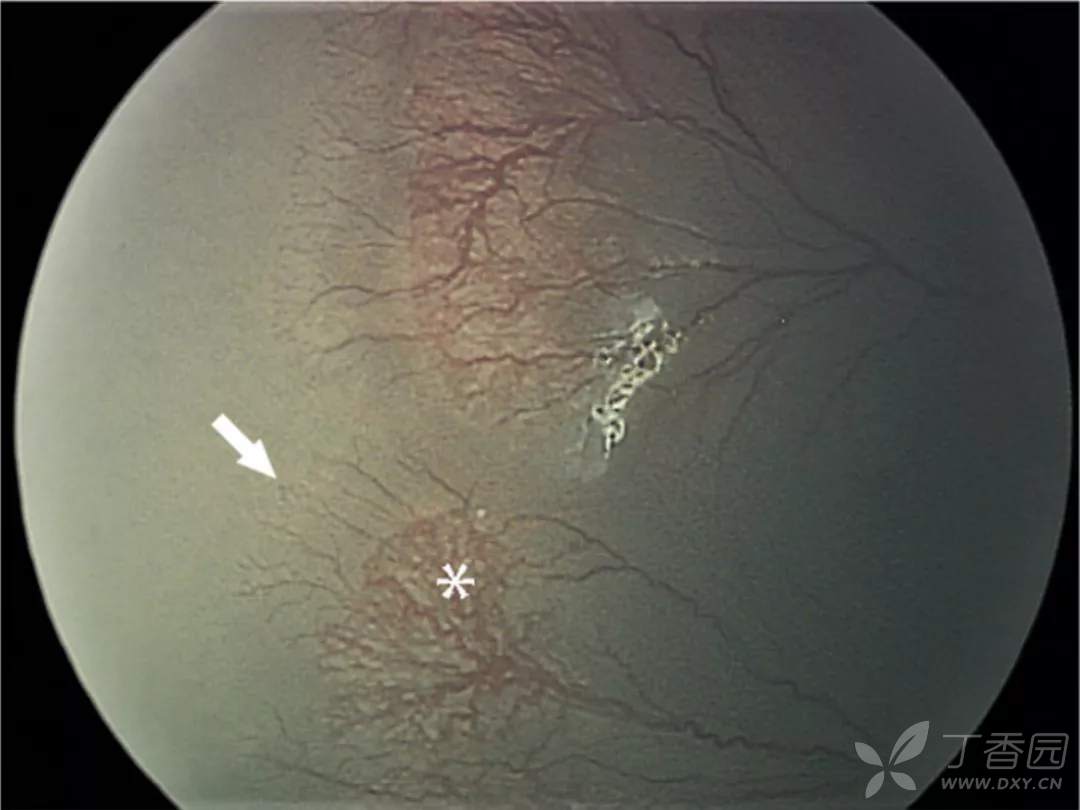

10、早产儿视网膜病变再活化

图. 既往矫正胎龄37周时抗VEGF治疗,矫正胎龄68周时发现周边无血管区视网膜血管化,伴再活化1期病变(白箭),原来嵴的位置可见多个环形血管襻(星号)。